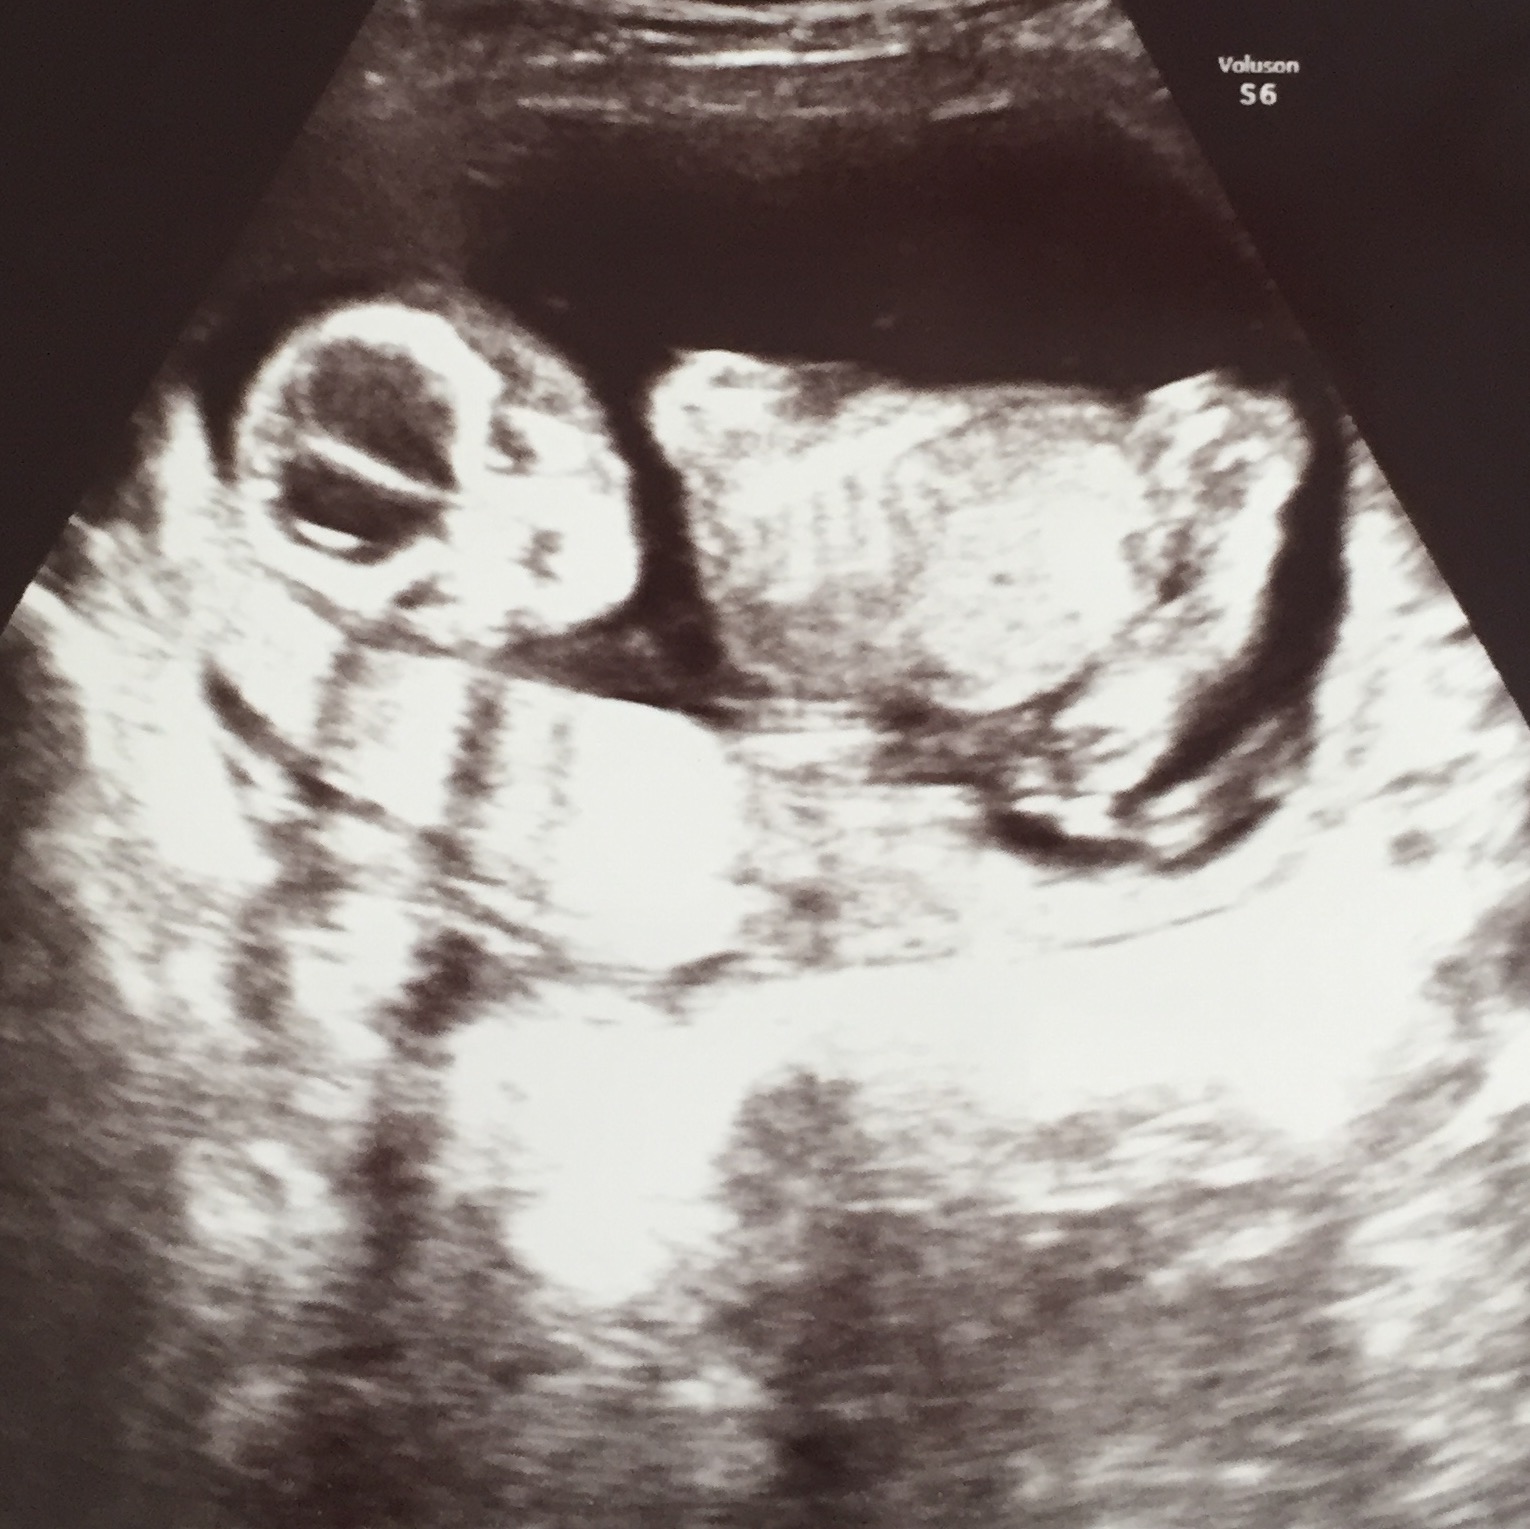

そして待ちに待ったエコー!

土曜日に行ったからか、全体的にあっさりめでしたが、旦那がものすごく感動してました(*´艸`*)

私もとても大きくなっていて感動!

頭からお尻が9cm、全身は多分15cmくらいと言われました。

後で調べると、15wの平均が10cm〜13cmらしいのでより少し大きめかな?

4Dも撮ってもらえましたが、なんと4Dに切り替えるタイミングで背中を向ける我が子( ;∀;)

ええええお顔見せてよおおおおお( ;∀;)

旦那は「えっこの一瞬の間に何が…」と残念そう。

エコー写真